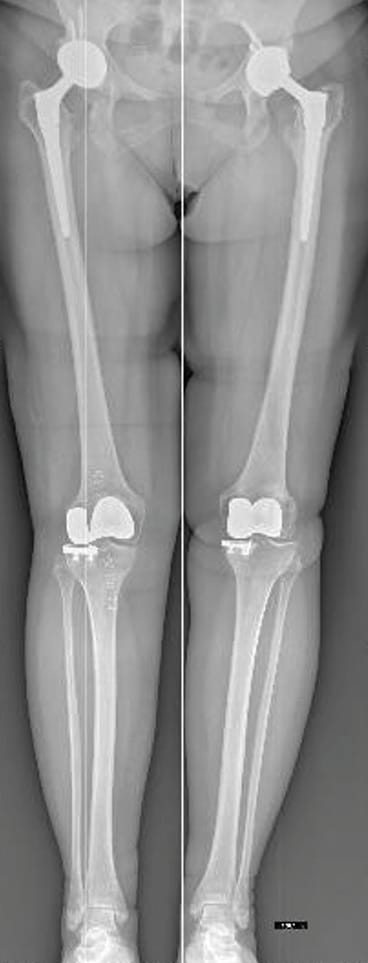

Isolated arthritis in the medial, lateral, or patellofemoral (PF) compartments of the knee can effectively undergo treatment with specialized unicompartmental implants: unicompartmental knee arthroplasty (UKA)—either medial or lateral—and patellofemoral arthroplasty (PFA). The simultaneous presence of arthritis in one tibiofemoral compartment and the patellofemoral joint typically warrants total knee arthroplasty (TKA) to address the entire knee structure. However, this approach may be considered excessive due to potential harm to unaffected compartments. Some experts suggest that symptomatic patellofemoral arthritis might be disregarded during a medial UKA procedure, particularly if only the medial facet of the patella is affected. Conversely, others advocate for TKA as the preferred solution in such cases. However, arthritis or painful Kellgren-Lawrence grade 3 or 4 chondromalacia in the medial or lateral compartment is usually regarded as a contraindication to PFA in PF arthritis treatment, making TKA the conventional approach (Figure 3).